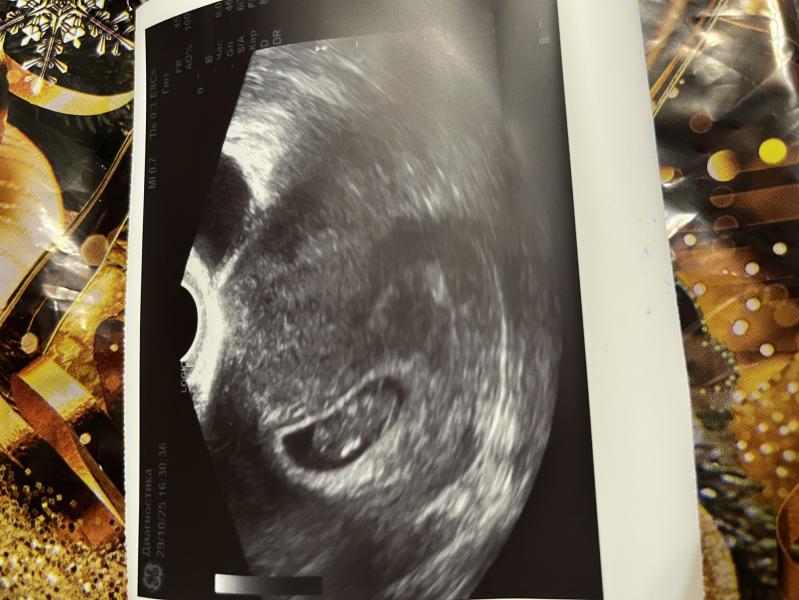

Развитие плода по УЗИ: опережение срока на 1,5 недели

Такой большой стал малыш🥺

Первый раз когда слушала сердечко , был со всем маленьким. А сейчас опережаем срок. По месячным 7,6 недель, а по узи ставят 9,1 недель